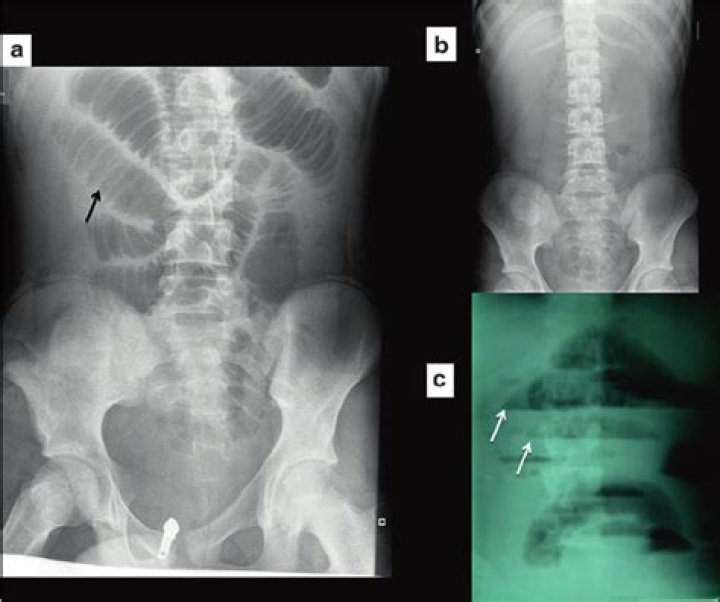

Closed-loop obstruction occurs when a segment of bowel is obstructed at two points along its course, resulting in progressive accumulation of fluid in gas within the isolated loop, placing it at risk for volvulus and subsequent ischemia (4,5).

In complete obstruction, loops of small bowel distend within 3-5 hours. A bowel larger than 3 cm in diameter is often associated with obstruction; gas and fluid are usually present in the distended small-bowel loops, and gas and fluid levels may be present at the same or different levels in the abdominal cavity.

These are partly determined by a knowledge of small and large bowel anatomy. See the page on normal Bowel Gas Pattern. Dilatation >3cm of the small bowel is considered abnormal, however the longer the segment of bowel that is dilated, the more likely bowel dilatation represents a genuine obstruction.

Will abdominal xray show gas?